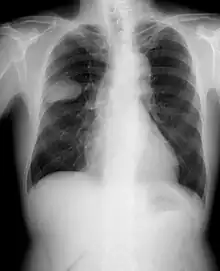

![]() | |

| Micrograph of a small-cell carcinoma of the lung showing cells with nuclear moulding, minimal amount of cytoplasm and stippled chromatin. FNA specimen. Field stain. | |